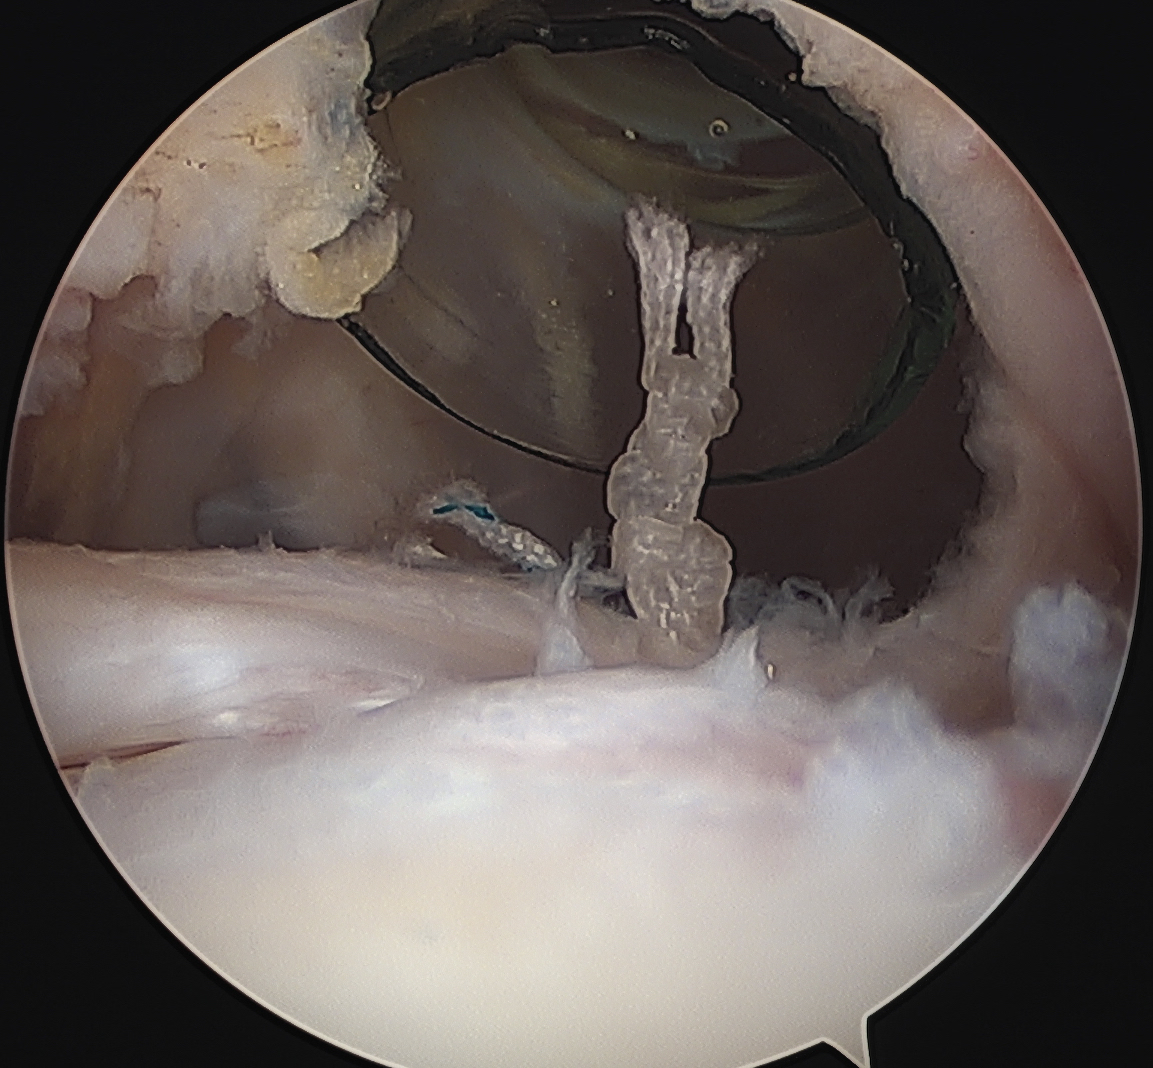

Arthroscopy

Medial subluxation of LBH with subscapularis tear

Subscapularis repair

Biceps pulley repair (coracohumeral ligament) +/- reconstruction +/- bicipital groove deepening